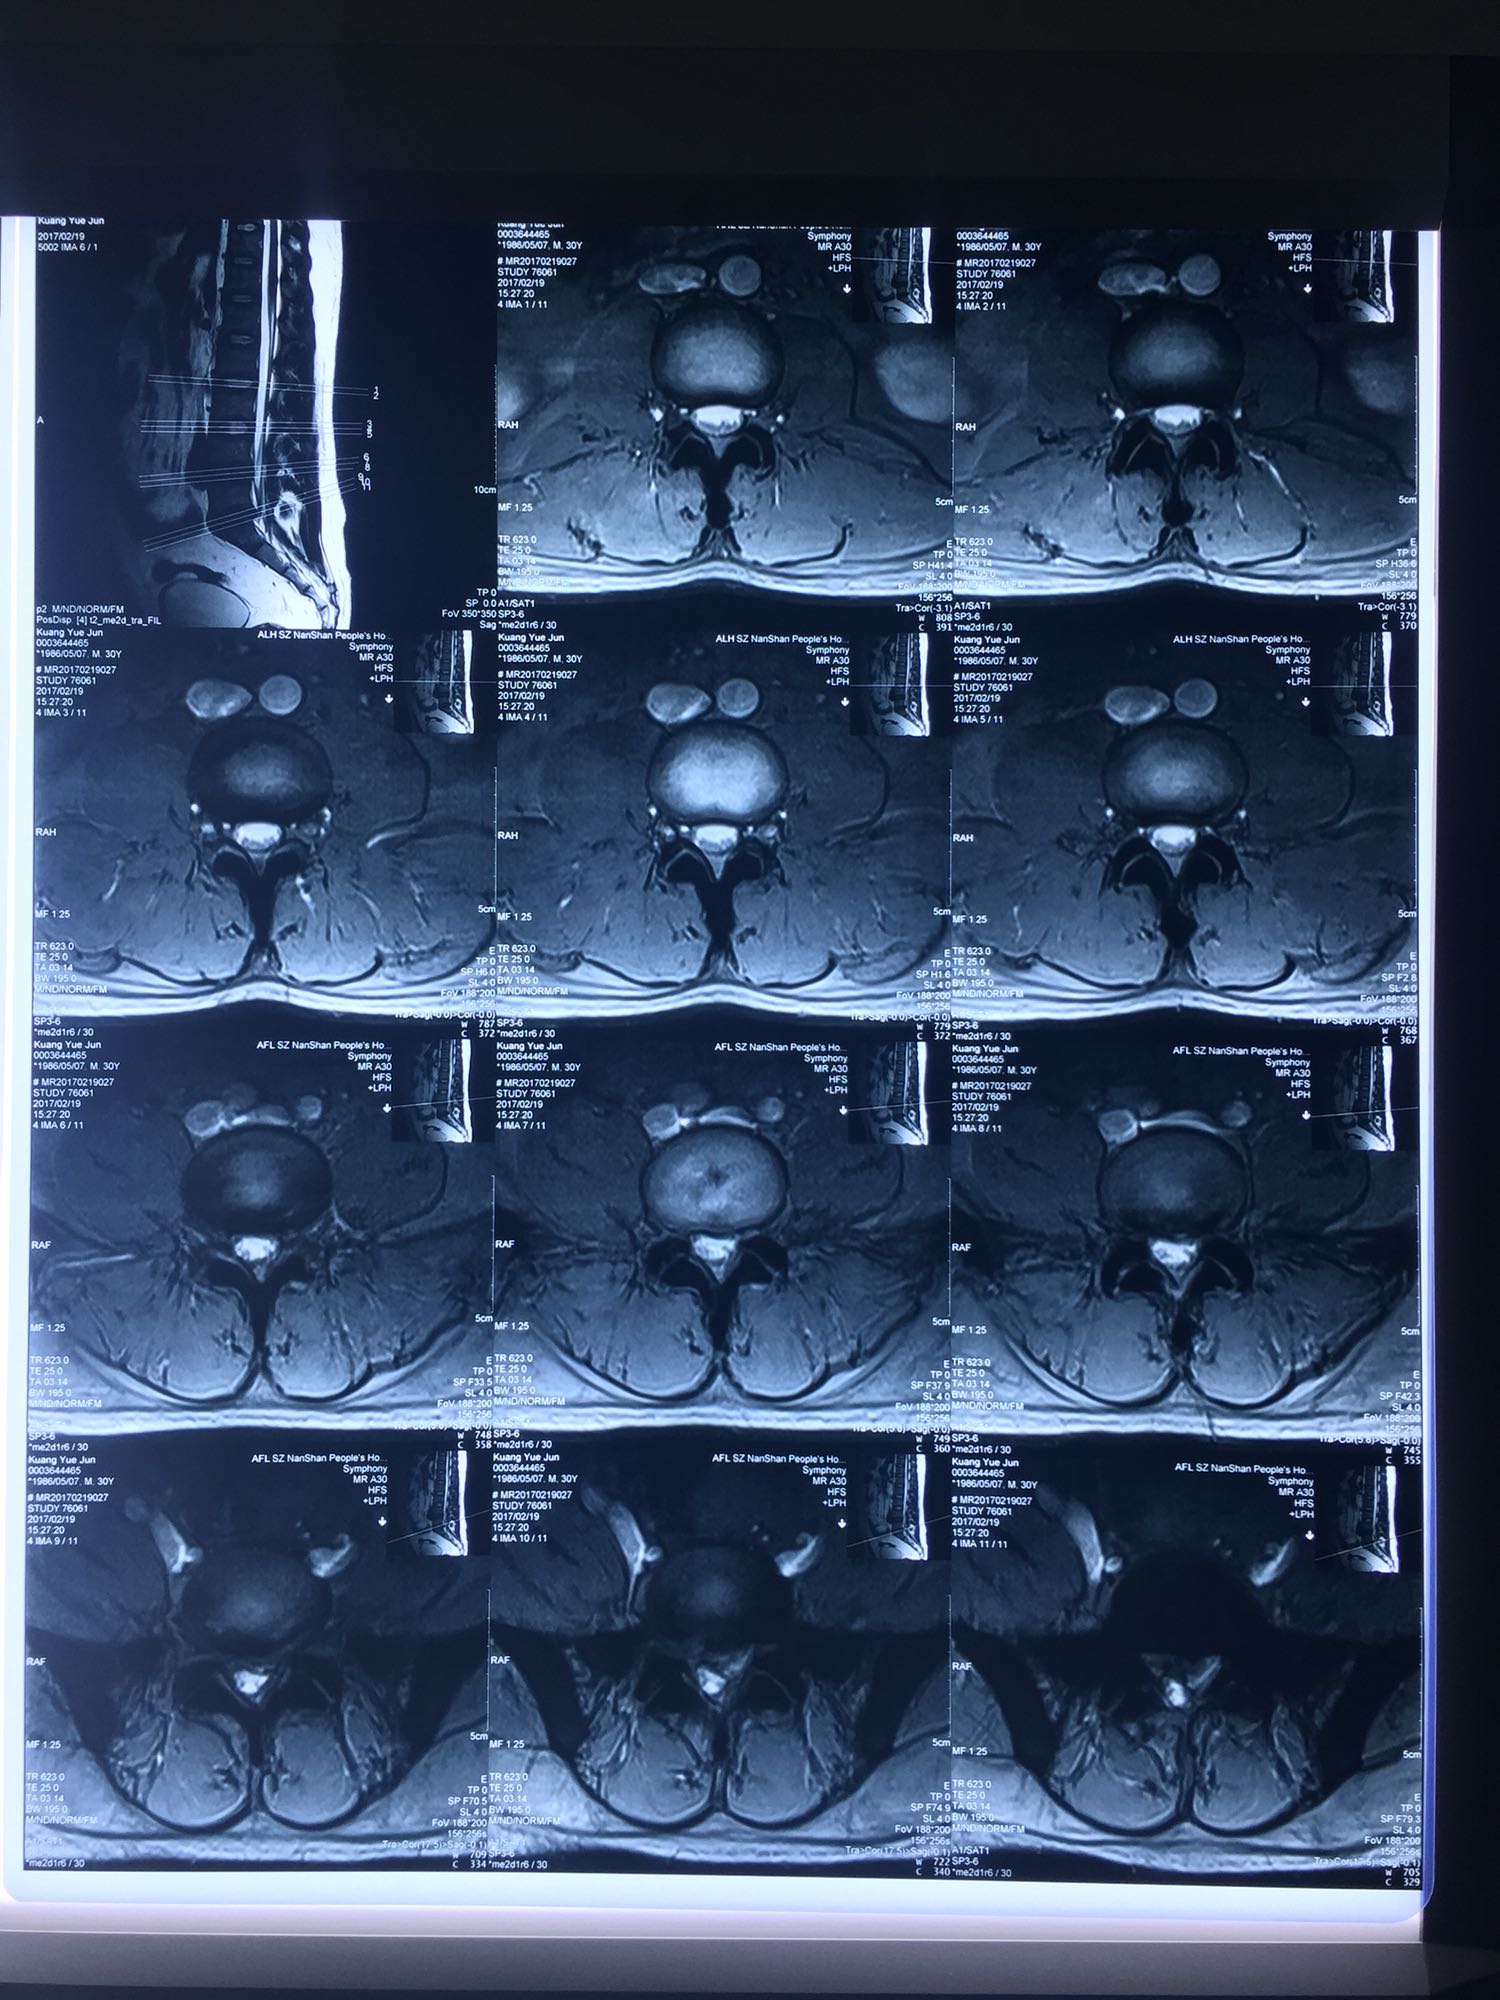

椎间孔镜下腰5骶1椎板间隙入路髓核摘除术

腰椎间盘脱出

邝X军,男性,30岁,因左下肢疼痛1天而入院。 1天前无明显诱因出现左下肢疼痛,程度较重,难以忍受,伴有行走困难。

腰骶部肌紧张,腰5骶1棘间及左侧椎旁有压痛及放散痛,左侧坐骨神经出孔处有压痛及放散痛,左侧足背外侧及足底部皮肤感觉麻木,左侧直腿抬高试验阳性(30度)。

诊断:腰5骶1椎间盘突出症 治疗方案:椎间孔镜下经椎板间入路髓核摘除术

术后患者疼痛完全消失